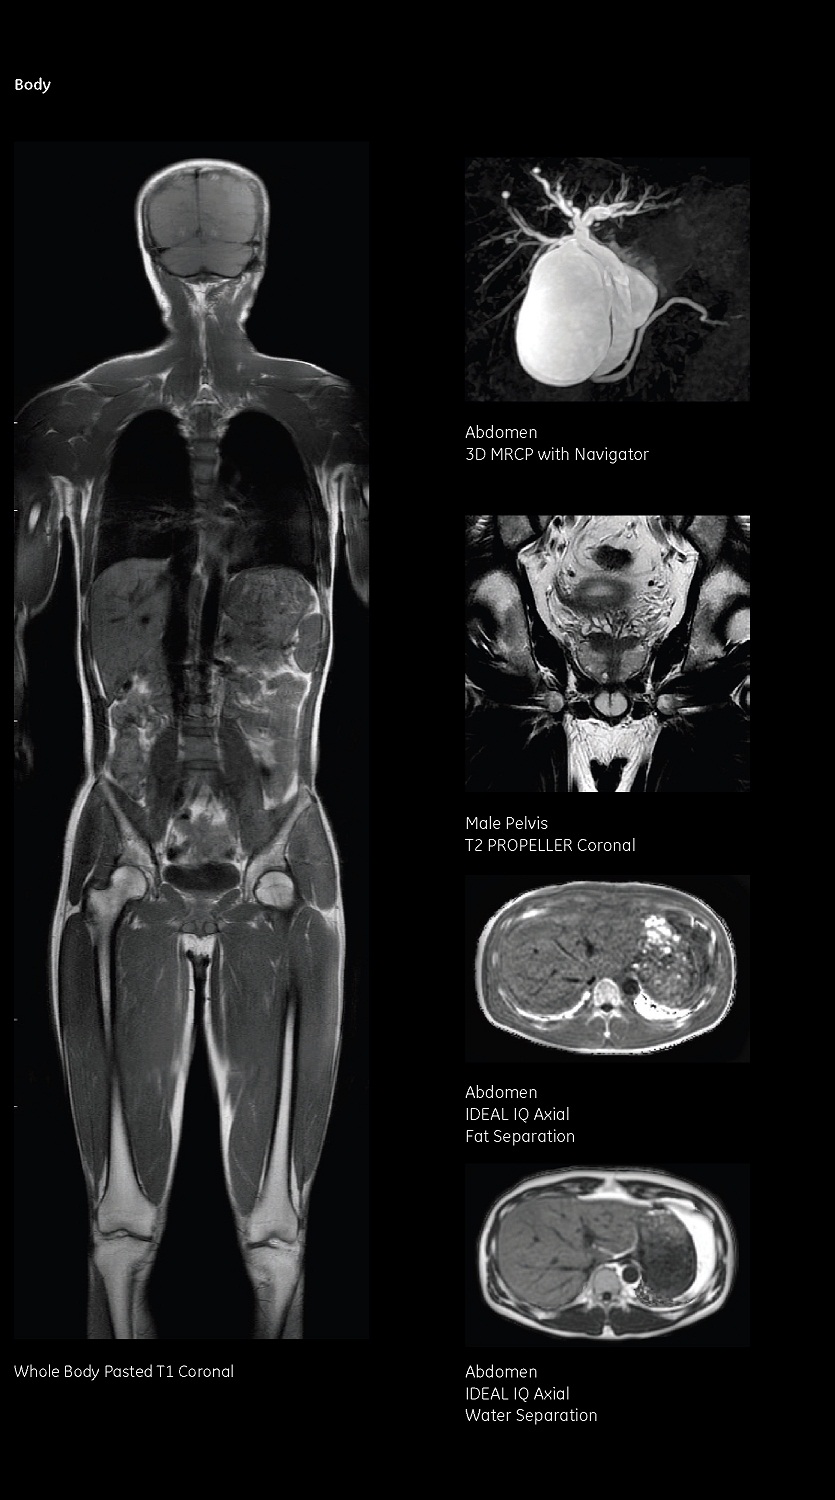

四、上腹部(肝、膽、胰、脾)

肝膽疾。和ㄟ^LAVA技術與多期動態(tài)增強掃描,在鑒別肝囊腫、海綿狀血管瘤、肝惡性腫瘤性病變方面優(yōu)于其他影像學檢查。

MRCP(胰膽管水成像)技術有著無創(chuàng)、無輻射的特點,在顯示胰、膽管系統(tǒng)疾病有不可取代的優(yōu)勢。胰腺疾。簩σ认俨∽內缂甭砸认傺、胰腺癌的顯示及周圍侵犯及轉移情況。

五、泌尿系統(tǒng)及盆腔

磁共振對前列腺疾病、女性盆腔疾病、膀胱腫瘤的顯示優(yōu)于其他影像學檢查。MRI極高的軟組織分辨率,及多種先進的成像方法,使得盆腔、男(女)性生殖系統(tǒng)病變得以很好的顯示。

泌尿系檢查從多角度觀察泌尿系平掃與水成像(MRU),使泌尿系的病變可清晰顯示,通過對其形態(tài)的觀察,可以對病變進行定位或定性的診斷,同時結合MR平掃及增強檢查,診斷將更為準確。

八、全身彌散成像技術(類PET)

全身彌散成像技術(WB-DWI)是一項全新的磁共振成像技術,在腫瘤篩查、良惡性鑒別診斷、腫瘤的分期及腫瘤治療的隨訪中具有很高的臨床價值。